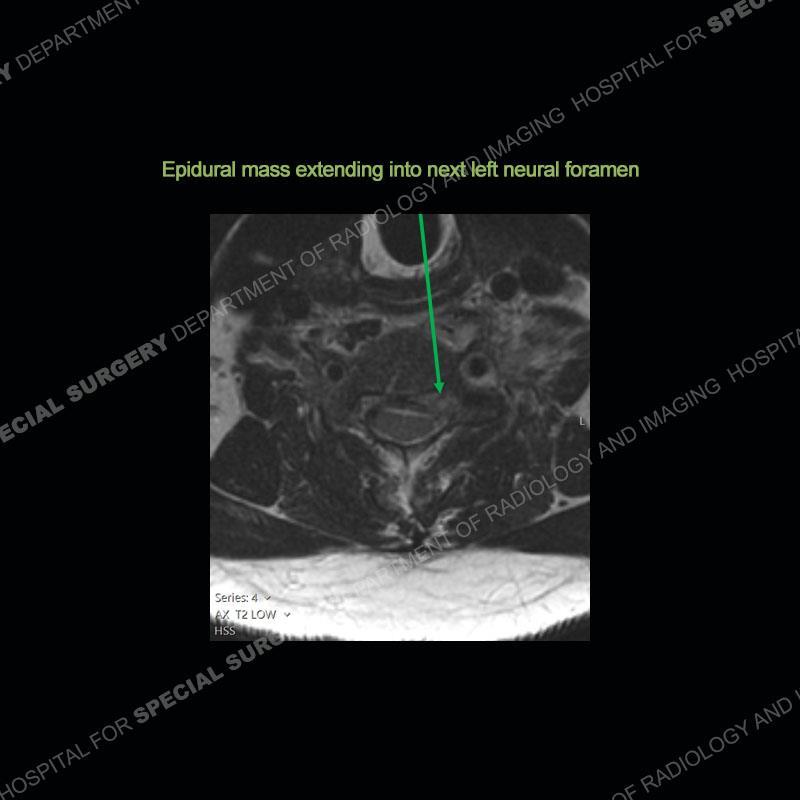

The radiographs demonstrate a prevertebral soft tissue fullness centered at C5-C6 that persists even on extension. There is a slight loss of disc height at C5-C6. The CT more readily shows the prevertebral soft tissue swelling at C5C6 where there is a punctate focus of gas. On the MRI, there is a marked amount of edema and a heterogeneous collection in the prevertebral soft tissue at C5-C6. Edema is present of the C5 and C6 vertebral bodies with a loss of the normal architecture about the disc space. A heterogeneous epidural collection has formed that causes compression of the spinal cord asymmetric to the left side and also precipitates severe left sided neural foraminal stenosis.